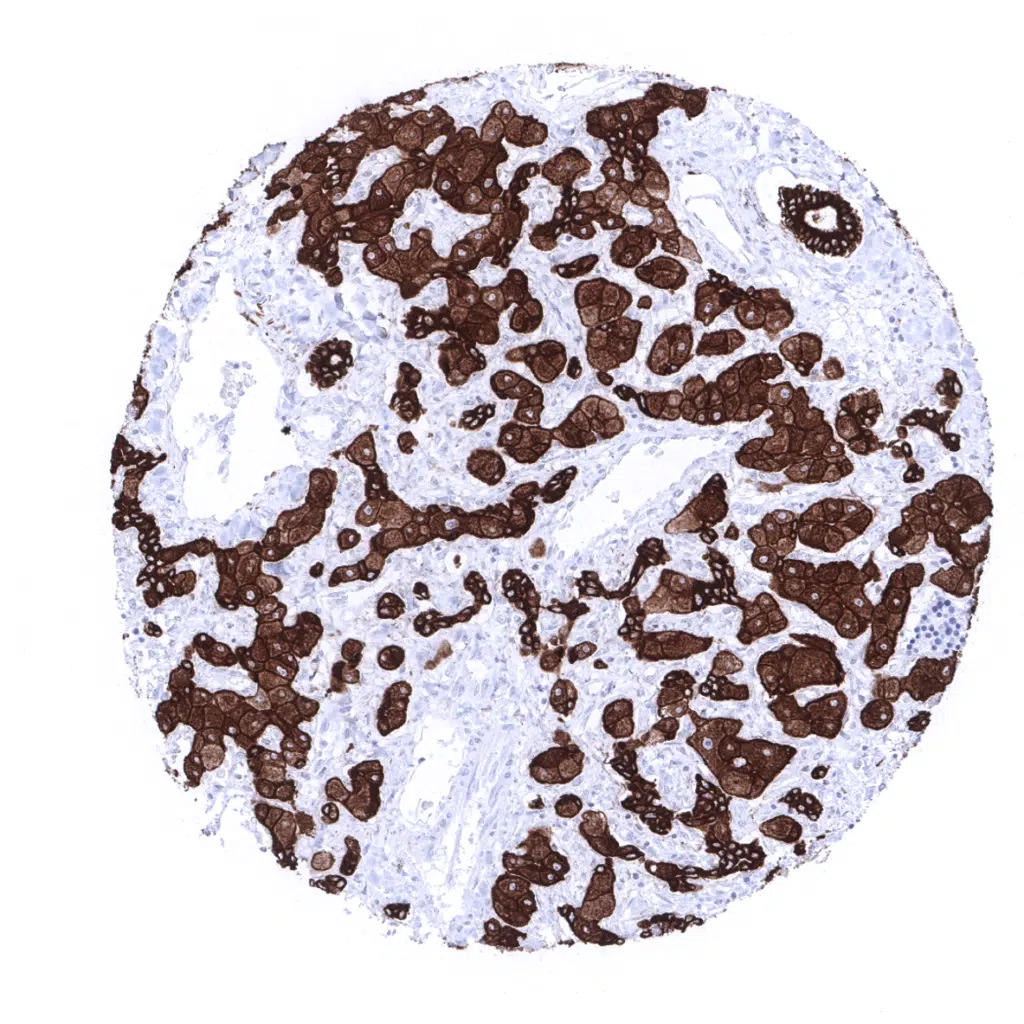

Strong diffuse pan Cytokeratin immunostaining in a pancreatic adenocarcinoma.

Strong diffuse pan Cytokeratin immunostaining in a pancreatic adenocarcinoma. In this case fibroblasts of demoplastic sroma reaction also stain pan Cytokeratin positive.